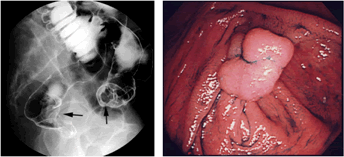

大腸がんを発見するための検査としては大腸全体をバリウムと空気でうつし出す注腸造影検査が広く行われてきました。しかし、近年では大腸内視鏡検査によって発見される大腸がんが増えてきています。大腸内視鏡は注腸造影よりも技術を必要とする検査で、苦痛をともなうこともありますが、病巣を直接観察できますし、病巣が発見されたら、生検という病巣部から小さな組織を採取する方法によって、がん細胞の有無を調べることができます。